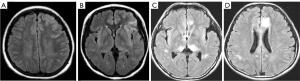

In this group of 18 patients, comprising 8 males and 10 females, the gender ratio was 10:8. The average age of onset was 56.2±12.8 years, ranging from 21 to 74 years, with a median disease duration of 90 days. All 18 patients underwent brain MRI during the acute stage, and 13 of them (72.2%) showed specific abnormalities. According to clinical semiology, the patients were categorized into 3 subgroups: MTLE-like seizure group (11 patients), FBDS group (6 patients), and MTLE-like seizure + FBDS group (1 patient). In the MTLE-like seizure group, brain MRI of 9 patients (9/11) showed abnormalities in the unilateral (7/9) or bilateral (2/9) hippocampus, sometimes involving adjacent structures such as the amygdala and parahippocampal gyrus. Seven of these patients exhibited swelling with mild hypointensity on T1WI, hyperintensity on T2 FLAIR (Figure 2), and normal or mild hyperintensity on DWI. The other two patients showed unilateral hippocampal atrophy and T2 FLAIR hyperintensity. One of these patients underwent MRS, which revealed a decreased NAA peak in the bilateral hippocampus. In the FBDS group, brain MRI of 3 patients (3/6) revealed unilateral (2/3) or bilateral (1/3) basal ganglia swelling, primarily involving the head of the caudate nucleus and the lenticular nucleus, with mild hyperintensity on T1WI, hyperintensity on T2 FLAIR, and normal or mild hyperintensity on DWI (Figure 3). One of these patients also underwent 18F-FDG PET-CT scan, which revealed increased FDG metabolism involving the bilateral lenticular nuclei. There was only one patient in the MTLE-like seizure + FBDS group, who initially manifested as MTLE-like seizure and developed FBDS later during the treatment. The brain MRI of this patient showed mild T2 FLAIR hyperintensity in the bilateral hippocampus.

Among the 18 cases, 9 were re-examined with brain MRI during the convalescent period, including 6 cases in the MTLE-like seizure and 3 in the FBDS group. All 9 cases showed a reduced range of lesions and decreased T2 FLAIR hyperintensity. The clinical and imaging features of anti-LGI1 encephalitis are presented in Tables 1,2.

Anti-LGI1 encephalitis typically affects two locations in imaging including hippocampus and basal ganglia, the former often presented MTLE-like seizures and cognitive impairment, and hippocampal atrophy was found in follow-up studies (21,22); the latter usually presented FBDS (23,24). Signal characteristics vary depending on the lesion location, disease course and severity. Hippocampal involvement usually manifests as edema with T1 hypointensity, T2 FLAIR and DWI hyperintensity in the acute phase, followed by hippocampal atrophy in the chronic stage. Basal ganglia involvement usually presents as hyperintensity (on T1WI, T2WI, T2 FLAIR, and DWI) in the acute phase, and atrophy in the chronic phase. Functional imaging techniques, such as 18F-FDG PET-CT, have improved AE diagnosis, offering higher sensitivity than MRI. Anti-LGI1 encephalitis is characterized by concurrent FDG hypermetabolism involving the basal ganglia and/or hippocampus and hypometabolism in neocortex. Hypermetabolism in the basal ganglia is related to FBDS (25).

In this study, among the 18 patients with anti-LGI1 encephalitis, nine cases involved the hippocampus with MTLE-like seizures, three involved the basal ganglia with FBDS, and one case presented both seizure types with bilateral hippocampus involvement. Additionally, MRS revealed decreased NAA peaks in the bilateral hippocampus in one case, while 18F-FDG PET-CT revealed hypermetabolism in bilateral basal ganglia in another. These findings are in line with previous studies (13,21,24,25), confirming that the basal ganglia and hippocampus are the most commonly affected locations in anti-LGI1 encephalitis and can be involved simultaneously. Functional neuroimaging may be helpful for early diagnosis.